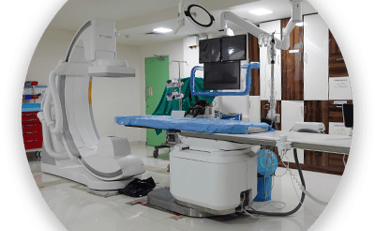

JJ Hospital is a forward-thinking healthcare center committed to providing accessible, affordable, and high-quality medical services to individuals and communities. Our team of experienced and compassionate doctors works together to deliver advanced treatments, patient-focused care, and innovative medical solutions. Equipped with modern technology and a holistic approach to healthcare, we offer a wide range of medical services while maintaining excellence in every procedure. From preventive care and diagnostics to specialized treatments, we aim to provide reliable and affordable healthcare for everyone.Write your text here...